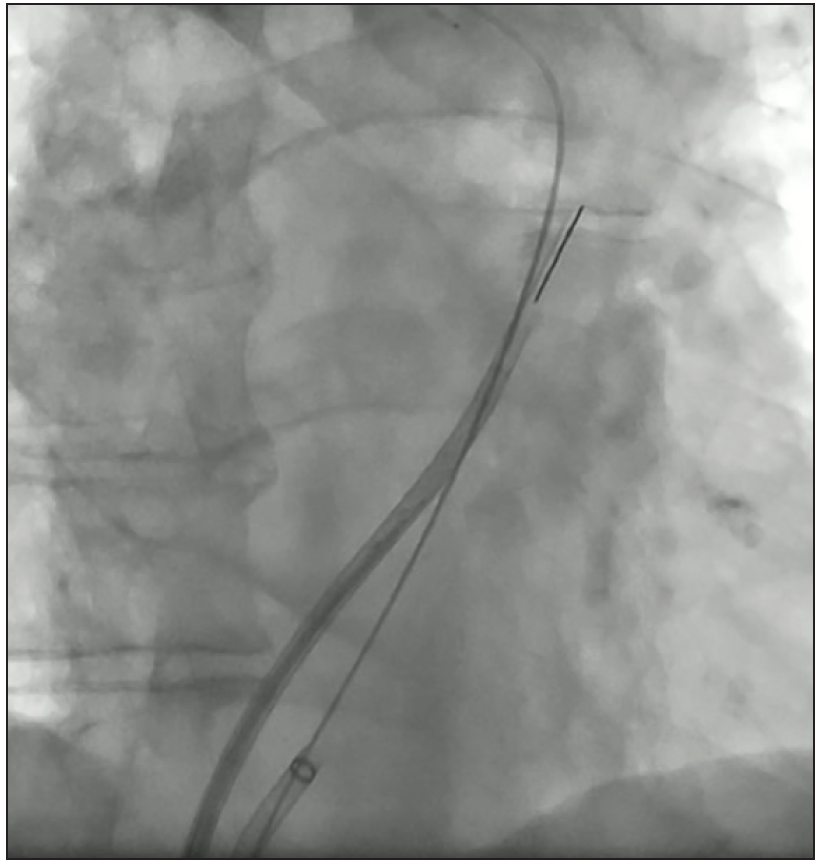

Figure 2. Once TSP and dilation of the septum have been performed, the delivery sheath is pulled back into the right atrium leaving a wire in the left upper pulmonary vein. The ICE probe is then advanced across the TSP, which is followed by readvancement of the delivery sheath.

A number of investigators have highlighted the utility of ICE for LAAO, with reported high efficacy and safety rates of 96.7% to 100%.36-39 Imaging can be accomplished from the right atrium, but only single-plane views can be achieved. Imaging can also be accomplished from the pulmonary artery, but with the same limitation of a single-plane view as well as the concern about manipulating the ICE probe through the right heart. Therefore, some investigators have proceeded to perform imaging from the left atrium, which can be accomplished via a single transseptal puncture (TSP) for both ICE and LAAO delivery systems (Figure 2). Once in the left atrium, the ICE probe can be manipulated to a series of positions (midleft atrium, anterior across the mitral valve, left upper pulmonary vein) to achieve views similar to that achieved by TEE multiplanes (Figure 3).